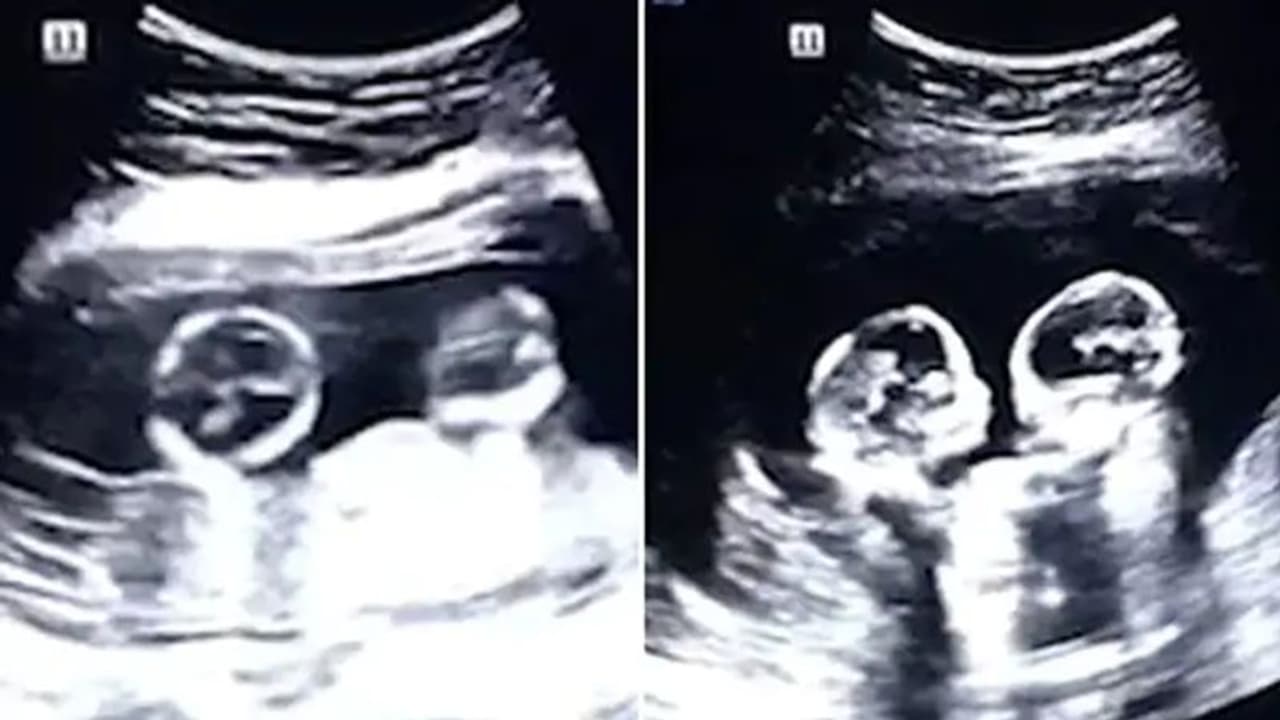

ತಾಯಿ ಹೊಟ್ಟೆಯೊಳಗೇ ಪರಸ್ಪರ ಹೊಡೆದು ಜಗಳವಾಡಿದ ಅವಳಿಗಳು| ಅಲ್ಟ್ರಾಸೌಂಡ್ ವೇಳೆ ಗಮನಕ್ಕೆ ಬಂತು ಅವಳಿ ಮಕ್ಕಳ ಜಗಳ| ತಂದೆ ಚಿತ್ರೀಕರಿಸಿದ ವಿಡಿಯೋ ವೈರಲ್

ಬೀಜಿಂಗ್[ಏ.17]: ತಾಯಿ ಹೊಟ್ಟೆಯಲ್ಲಿದ್ದ ಅವಳಿ ಮಕ್ಕಳು ಹೊಡೆದಾಡಿಕೊಂಡು ಜಗಳೋವಾಡುತ್ತಿರುವ ವಿಡಿಯೋ ಒಂದು ಸಾಮಾಜಿಕ ಜಾಲತಾಣಗಳಲ್ಲಿ ವೈರಲ್ ಆಗುತ್ತಿದೆ. ಅಧಿಕ ಸಂಖ್ಯೆಯಲ್ಲಿ ಈ ಅಲ್ಟ್ರಾಸೌಂಡ್ ವಿಡಿಯೋ ವೀಕ್ಷಿಸಲಾಗುತ್ತಿದ್ದು, ಪ್ರೇಕ್ಷಕರು ಇದನ್ನು ಬಹಳಷ್ಟು ಇಷ್ಟ ಪಡುತ್ತಿದ್ದಾರೆ.

ಇದು ಚೀನಾದಲ್ಲಿ ನಡೆದ ಘಟನೆಯ ವಿಡಿಯೋ ಎನ್ನಲಾಗಿದೆ. 2018ರಲ್ಲೇ ಇದು ಚೀನಾದಲ್ಲಿ ಶೇರ್ ಮಾಡಲಾಗಿತ್ತು ಎಂದು ಮಾಧ್ಯಮಗಳು ವರದಿ ಮಾಡಿವೆ. ನಾಲ್ಕು ತಿಂಗಳ ಗರ್ಭಿಣಿ ಮಹಿಳೆಯ ಅಲ್ಟ್ರಾಸೌಂಡ್ ವಿಡಿಯೋ ಇದಾಗಿದೆ. ಪರೀಕ್ಷೆಗೆಂದು ಆಸ್ಪತ್ರೆಗೆ ತೆರಳಿದ್ದ ವೇಳೆ ಅವಳಿ ಮಕ್ಕಳು ಪರಸ್ಪರ ಮುಖಕ್ಕೆ ಹೊಡೆದು ಜಗಳವಾಡುತ್ತಿರುವುದು ಗಮನಕ್ಕೆ ಬಂದಿದೆ. ಆ ಕೂಡಲೇ ಮಕ್ಕಳ ತಂದೆ ಟಾವೋ ಈ ವಿಡಿಯೋ ಚಿತ್ರೀಕರಿಸಿದ್ದಾರೆ.

ಚೀನಾದ ಸ್ಥಳೀಯ ಮಾಧ್ಯಮಗಳಿಗೆ ಪ್ರತಿಕ್ರಿಯೆ ನೀಡಿರುವ ಮಕ್ಕಳ ತಂದೆ 'ಹೊಟ್ಟೆಯೊಳಗಿದ್ದ ಮಕ್ಕಳು ಬಹಳಷ್ಟು ಸಮಯ ಪರಸ್ಪರ ಹೊಡೆದಾಡಿಕೊಂಡಿದ್ದವು' ಎಂದಿದ್ದಾರೆ. ಈ ವಿಡಿಯೋ 2 ಮಿಲಿಯನ್ ಗೂ ಅಧಿಕ ಮಂದಿಯಿಂದ ವೀಕ್ಷಿಸಲ್ಪಟ್ಟಿದೆ.

ಈಗ ಮಕ್ಕಳು ಜನಿಸಿದ್ದು, ಚೆರಿ ಹಾಗೂ ಸ್ಟ್ರಾಬೆರಿ ಎಂದು ನಾಮಕರಣ ಮಾಡಿದ್ದಾರೆ. ಹೀಗಿದ್ದರೂ ಈ ವಿಡಿಯೋ ಇವತ್ತಿಗೂ ಸೋಶಿಯಲ್ ಮೀಡಿಯಾದಲ್ಲಿ ಬಹಳಷ್ಟು ಹರಿದಾಡುತ್ತಿದೆ. 'ಹೊಟ್ಟೆಯೊಳಗೇ ಹೀಗೆ ಜಗಳವಾಡಿದ್ದಾರೆ ಆದರೆ ಹೊರ ಬಂದ ಬಳಿಕ ಪರಸ್ಪರ ಪ್ರೀತಿಯಿಂದ ಇರುತ್ತಾರೆ' ಎಂದು ವೀಕ್ಷಕನೊಬ್ಬ ಕಮೆಂಟ್ ಮಾಡಿದ್ದಾನೆ.